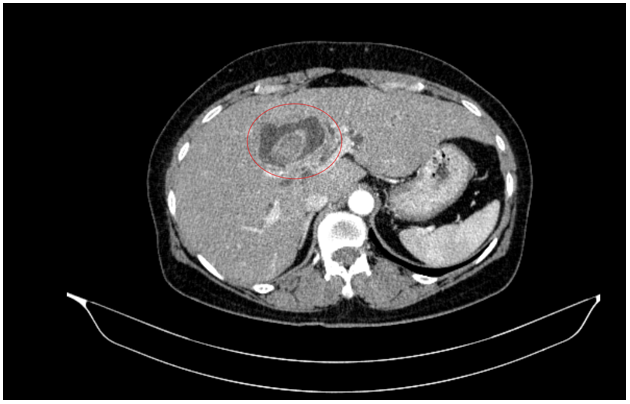

Sau đó bệnh nhân được nội soi dạ dày - đại tràng phát hiện đại tràng lên có khối lồi kích thước ~2.5cm, bề mặt nham nhở, cứng dễ chảy máu. Sinh thiết 03 mảnh. Giải phẫu bệnh: Ung thư biểu mô tuyến.

Hình 3. Tổn thương khối lồi xuất hiện ở vùng đại tràng lên

Nội soi đại tràng (thời điểm trước phẫu thuật T2/2025): Đại tràng lên có khối lồi kích thước ~2.5cm, bề mặt nham nhở, cứng dễ chảy máu.